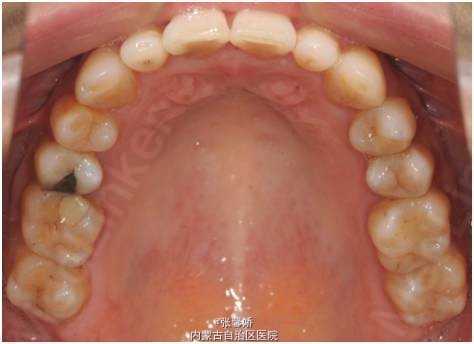

查体 辅查

上中线右偏1mm,A2、D4反合,A2、B2畸形牙偏小,拥挤度上颌4mm、下颌6mm。Spee曲线:左侧3mm,右侧2.5mm

牙列中度拥挤;A2、D4反合 处理:时代天使隐形矫治器矫治 拔除C8、D8 适当下前牙邻面去釉 排齐整平上下牙列,改正A2、D4反合 治疗时间2年左右,矫治后牙齿排列整齐,咬合关系良好,患者满意。